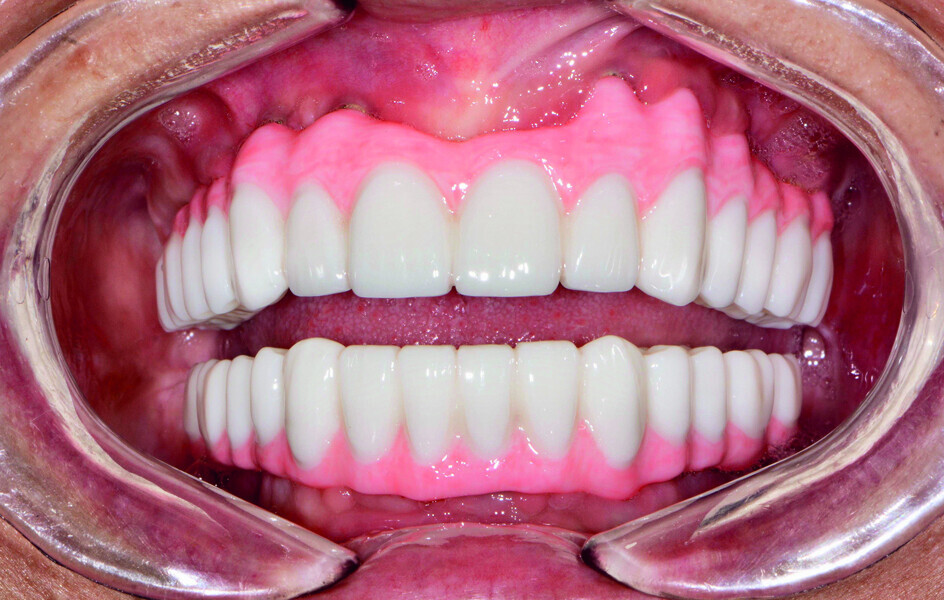

Fig. 21: Post-op retracted open-bite view.

Fig. 22: Post-op retracted closedbite

view.